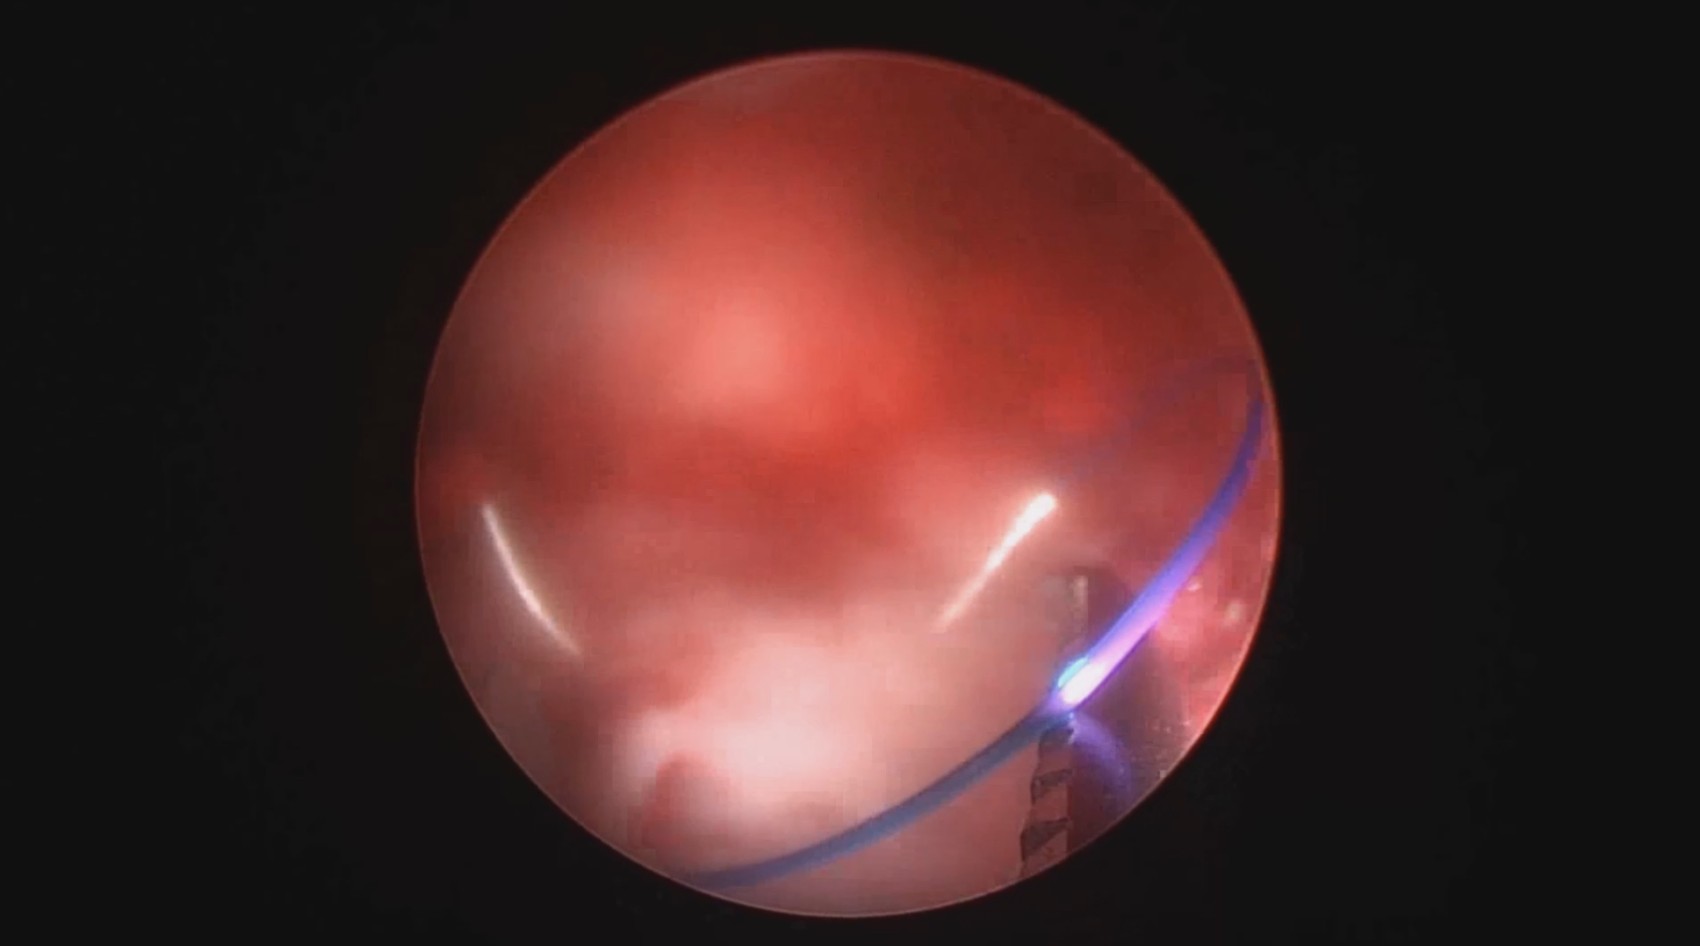

患者39岁,G4P2,顺产2次。2025年2月因异常子宫出血,阴道出血淋漓不净1+月行宫腔镜检查及内膜活检,病检为子宫内膜增生(无非典型)伴息肉形成。2025年3月,行经第3天,月经量大伴腹痛,要求放置曼月乐并固定。宫腔镜见内膜杂乱,脱落不全,吸刮内膜送病检,4-0不可吸收线将曼月乐环缝合固定于宫腔上段后壁。术中打结、推结很困难,放弃打结,留较长线尾在宫颈管,必要时可牵拉线尾调整节育环位置,只要缝合到子宫肌层,肌肉的卡压阻力可以起到固定作用,继续探索不用打结推结的固定方法。术后多次复查B超,子宫偏大,7.7cm*6.6cm*7.8cm,环顶端距宫底3cm。